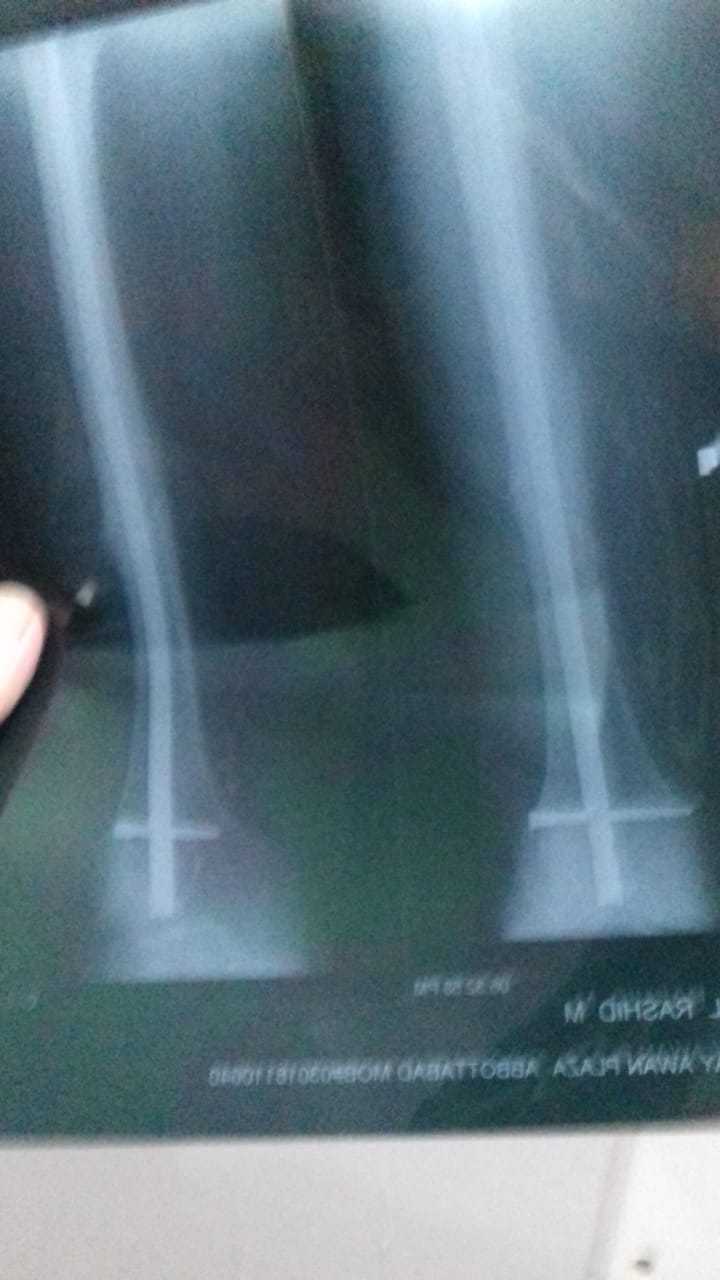

Please tag to an orthopedic surgeon.. My father age 60 had femur shaft fracture in Dec 2019 about 6 months ago where thigh bone has been broken in a angled line as shown in initial attached x ray. Dr. Implanted a rod with support in knee. In first 2 months he suffered from anxiety, but now he just feel uncomfortable in knee when he walk fastly or go up stairs. Now I attached today's x report could you please tell me the stage of healing process? Today one orthopedic surgeon advised that rod need to remove after couple of weeks because this rod is Biger than the usual used for these surgeries. But the surgeon who implanted gave us time period of one year to remove the rod. .should we go for rod removal? rod. I am attaching prescription and x ray in comments.

The nail is bending and the fracture line is visible,it is better to use cruthes while walking and wait for another six months

it's retrograde femur nailing. not a very poor procedure as it can damage knee articular cartilage. the nail is bent and as it seems there is shining callus which is going into consolidation. if weight bearing is painful then use a zimmer frame otherwise no issue. remove the nail after 1 year post op

This is retrograde nail and is done by opening up knee joint... So the distal part sometimes create problem with knee... Its realy to rem9ve the naip, so please avaoid stressea on stairs and squatting postures... Keep in touch with surgeon to get it removed early as the union is achieved fully

rod should be removed after 12 to 18 months ,dont remove it before,size is adequate,thanks